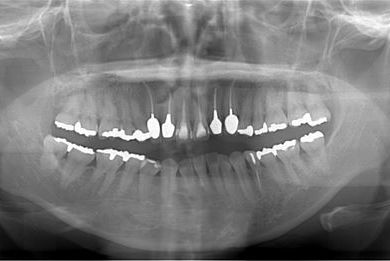

治療後

• 治療後